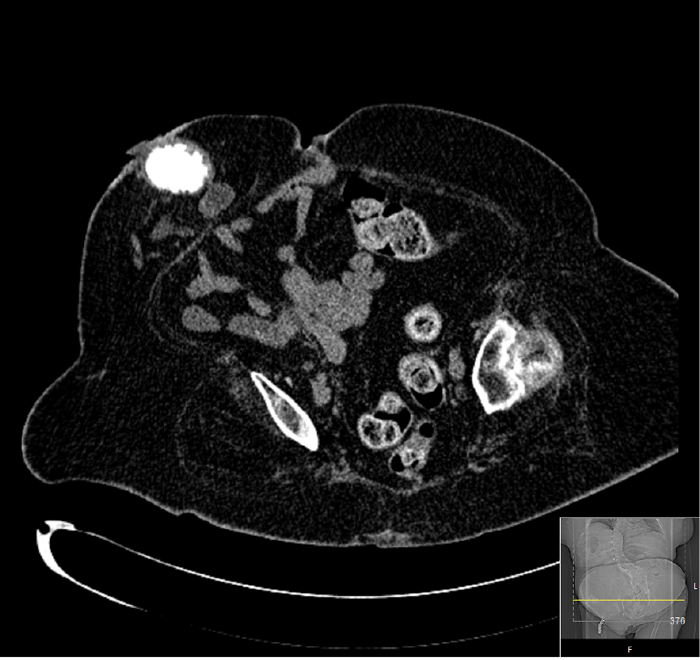

A 51-year-old obese patient with spina bifida, epilepsy, left ventricular dysfunction and lifelong warfarin due to a deep vein thrombosis (DVT) had an ileal conduit stone noted as an incidental finding on a CT scan (Figure 1). A 6mm stone was present in the right lower pole. Her urine was colonised with pseudomonas and she was MRSA positive.

Figure 1: CT scan showing ileal conduit stone.

Under general anaesthesia, a nephroscope was used to fragment the stone in situ which appeared visually clear. This was a technically difficult procedure as the stone was freely mobile in the conduit.

Fragmentation was achieved but a postoperative CT demonstrated a significant residual burden (Figure 2).

Figure 2: CT scan immediately postoperative.